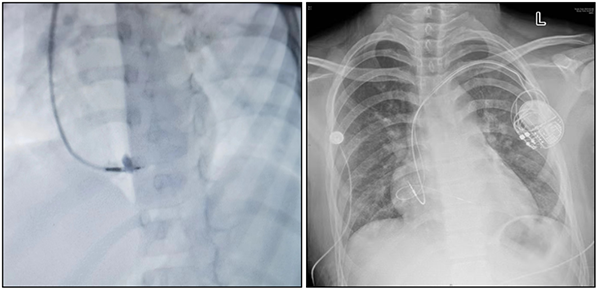

自2020年以来,中国仅有清华大学第一附属医院、上海儿童医学中心、北京安贞医院等少数医院小儿心脏科开始开展此先进手术技术,标志着中国在儿童心脏病治疗技术方面的进步和创新。2023年2月,省立医院儿科主任、小儿心脏科主任韩波教授带领团队,成功为一名13岁三度房室传导阻滞伴左室扩大的患者植入了山东省首例LBBAP模式的双腔抗核磁心脏永久起搏器,手术顺利成功,各项指标恢复良好。截至目前,科室已完成LBBAP手术9例,其中最小1例患儿年龄3岁,所有病例均顺利完成,无手术并发症发生。团队通过对儿童左束支区域起搏技术的初步探索发现,左束支区域起搏术后心电图 QRS 波时限均保持较窄,起搏参数良好稳定,患儿左心室内径较比术前明显缩小且心功能均保持良好。结合国内外少量医学中心的研究报告,目前左束支区域起搏技术在儿童中的运用是安全可行的。

省立医院小儿心脏科在韩波教授带领下,2003年在省内率先开展儿童临时起搏器植入术治疗儿童暴发性心肌炎并完全性房室传导阻滞,2004年在省内率先开展儿童起搏器植入术治疗完全性房室传导阻滞与病态窦房结综合征,2016年在省内率先植入儿童双腔永久起搏器,2018年完成省内首例儿童植入式心脏复律除颤器(ICD)植入术,同年植入省内首例儿童心外膜永久起搏器,2022年在省内率先植入儿童双腔抗核磁永久起搏器,迄今已完成先心病介入治疗术、经导管射频消融术及起搏器植入术7000余例,其中儿童起搏器植入术100余例,是山东省开展小儿心脏病介入手术时间最早、种类与数量最多、质量最好的科室,跻身全国先进行列。左束支区域起搏技术的创新性应用标志着小儿心脏科在起搏器的植入技术方面再上新台阶,在国内小儿缓慢型心律失常和心力衰竭治疗领域处于领先水平。此成就得益于医院的大力支持和小儿心脏科专家团队丰富的临床经验和对先进医疗技术的深入理解,致力于探索和应用新的治疗方法,为儿童心脏病患者提供更高水平的医疗服务。